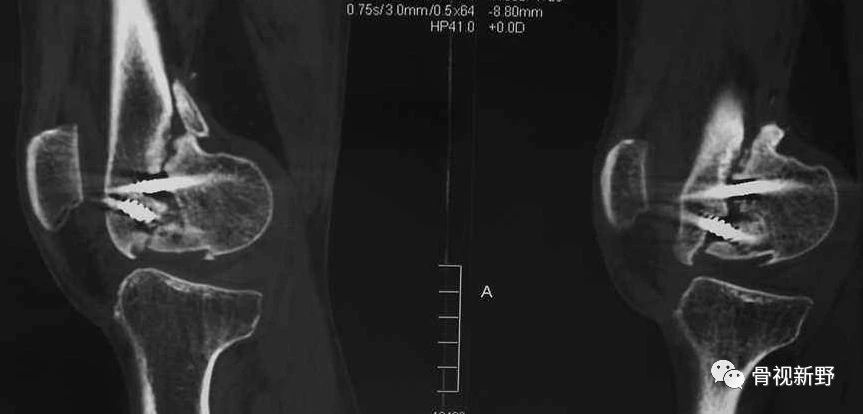

影像诊断:部分Hoffa骨折X线片不能提供明确的诊断,漏诊率较高。需要CT或MRI检查,并根据患者的病史、查体及影像学检查予以确诊。

部分Hoffa骨折普通X光片易漏诊

CT扫描在矢状位、轴位容易发现骨折及骨折线的走形方向